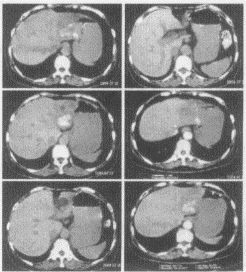

| 女,60岁,上腹痛10个月,近来加剧。疼痛以夜间为重,坐起可缓解,向背部放射,胃纳差,近期体重下降。实验室检查正常。 |

3.患者所做检查图如下,你考虑为何种疾病?![]() |

| 4.你的诊断依据是那些? |

| 正确答案:1.ABD;2.ABD;3.C;4.BCDE;5.B;6.ABC |